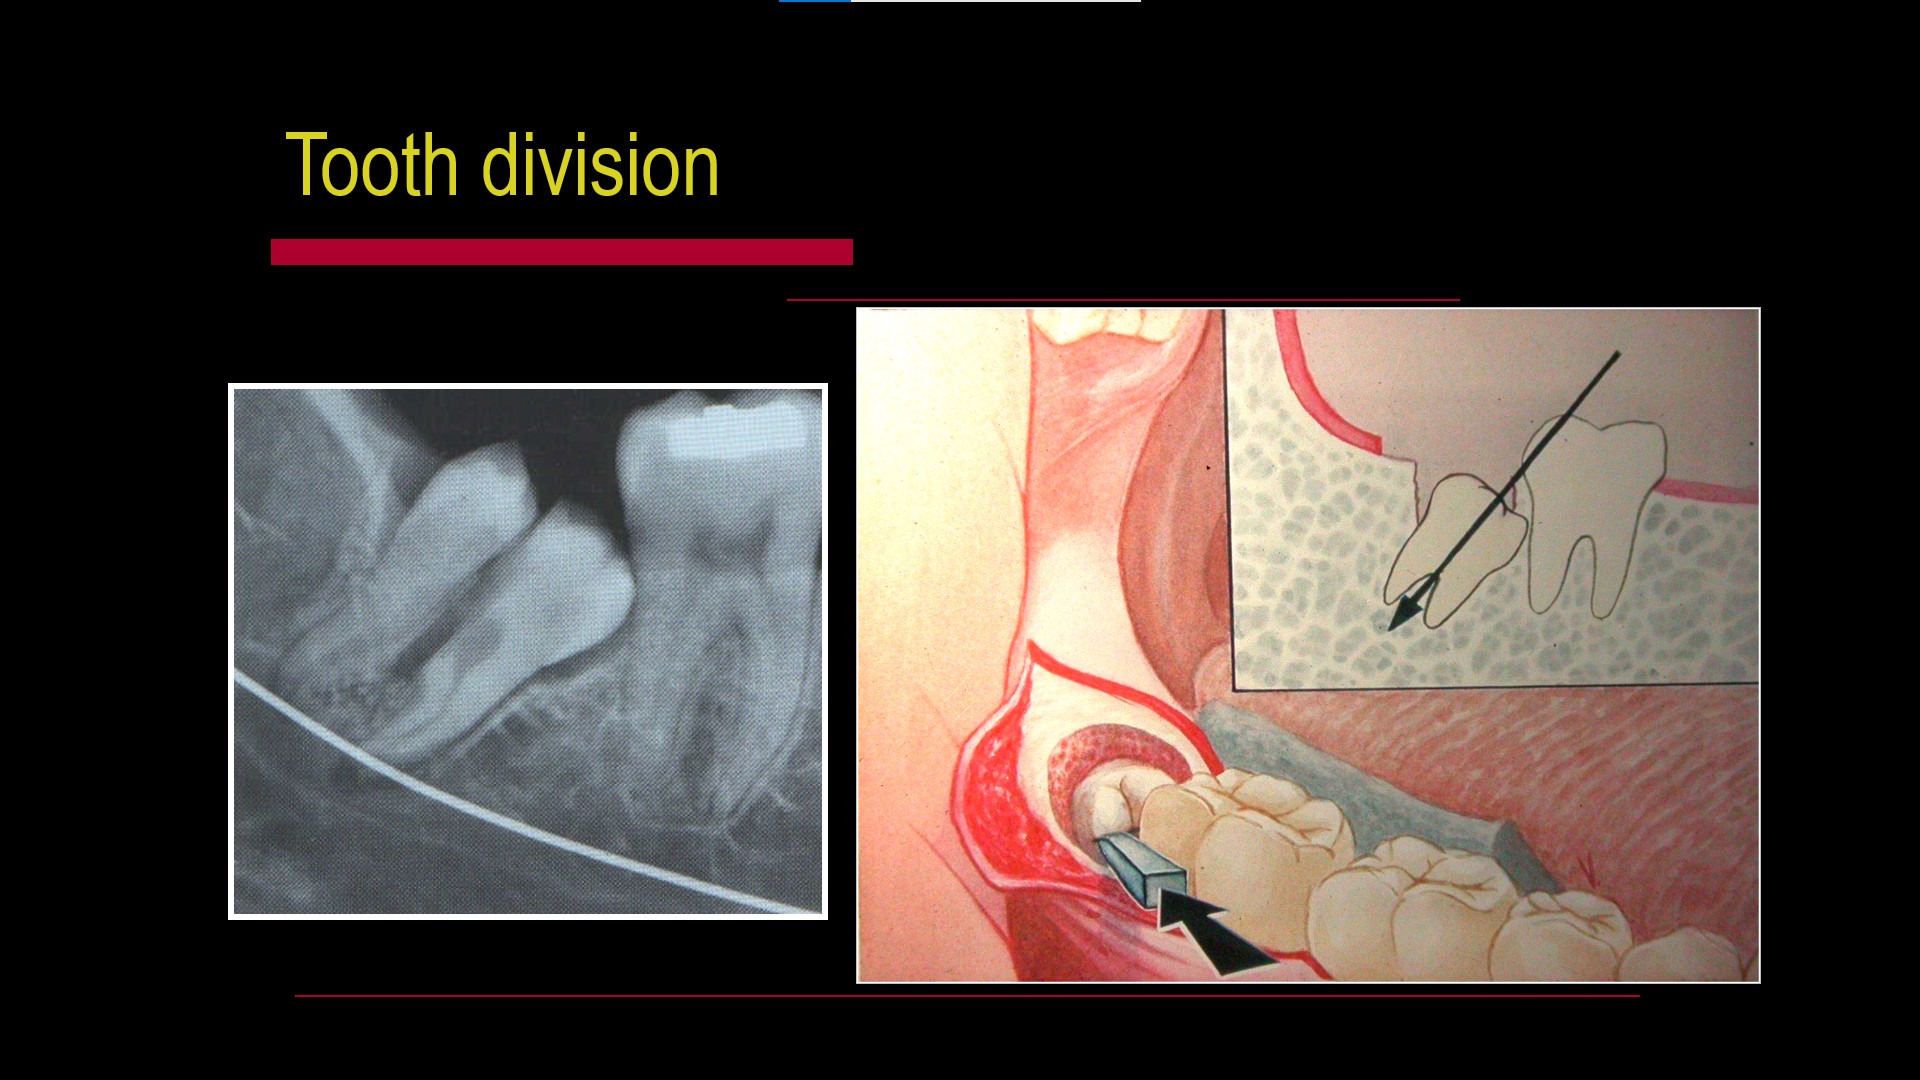

Impacted teeth

Oral Surgical Procedures